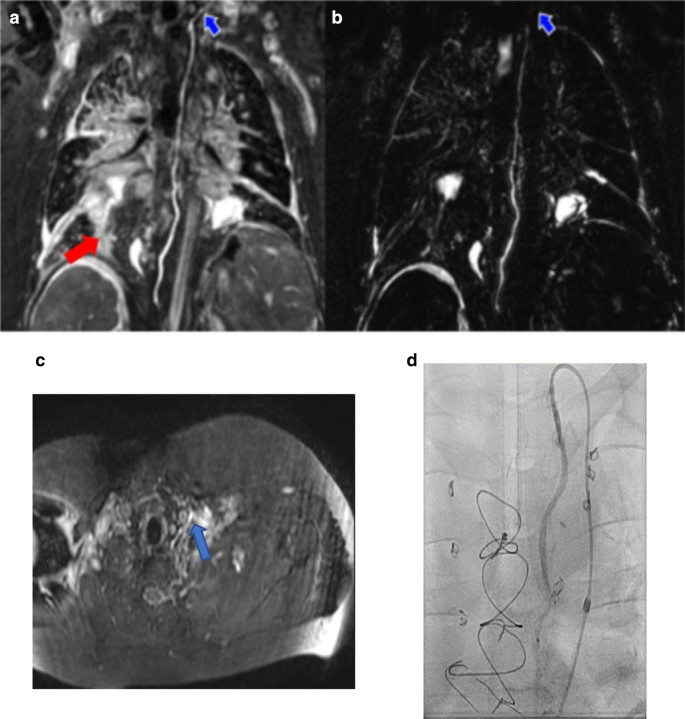

a Maximum intensity projection (MIP) of a T2w scan with the entire thoracic duct (blue arrows) visualized. b Curved planar reformat of the same patient (a) showing the thoracic duct with 3D-bSSFP, also visualized in its entirety. c MIP of a T2w lymphatic scan in another patient, with loss of thoracic duct visualization in the upper thorax (red arrow), while (d) 3D-bSSFP showed the complete pathway of the duct

With 3D-bSSFP alone, we clearly tracked the thoracic duct and identified areas of leakage in some severe cases where 3D-bSSFP complemented T2w for confirmation of leakage sites. Improved tracking in 3D-bSSFP was likely due to higher SNR and cardiac-triggered acquisition along with dual-phase 3D-bSFFP whole-heart imaging [30, 31], an innate strength of this sequence (Fig. 3 and Additional files 2, 3, 4 and 5). However, image acquisition with either single or dual phase did not impact lymphatic visualization.

We were able to visually track complete thoracic duct pathway more often with 3D-bSSFP (54%) than with T2w scans (24%). Incomplete visualization in T2w images was attributed to (1) poor or incomplete tracking of T2w signal and (2) loss of signal in the retrocardiac region. The most common sites of signal loss were in the mid-thorax region where the thoracic duct crosses below the carina and prior to entering the supraclavicular region. This signal loss may have been in part due to cardiac or respiratory motion during the long TSE readout and low SNR and spatial resolution offered by the heavily T2w sequence. Cardiac-triggered scans with a TSE readout optimized for reduced motion sensitivity may be used to minimize retrocardiac signal loss [29].